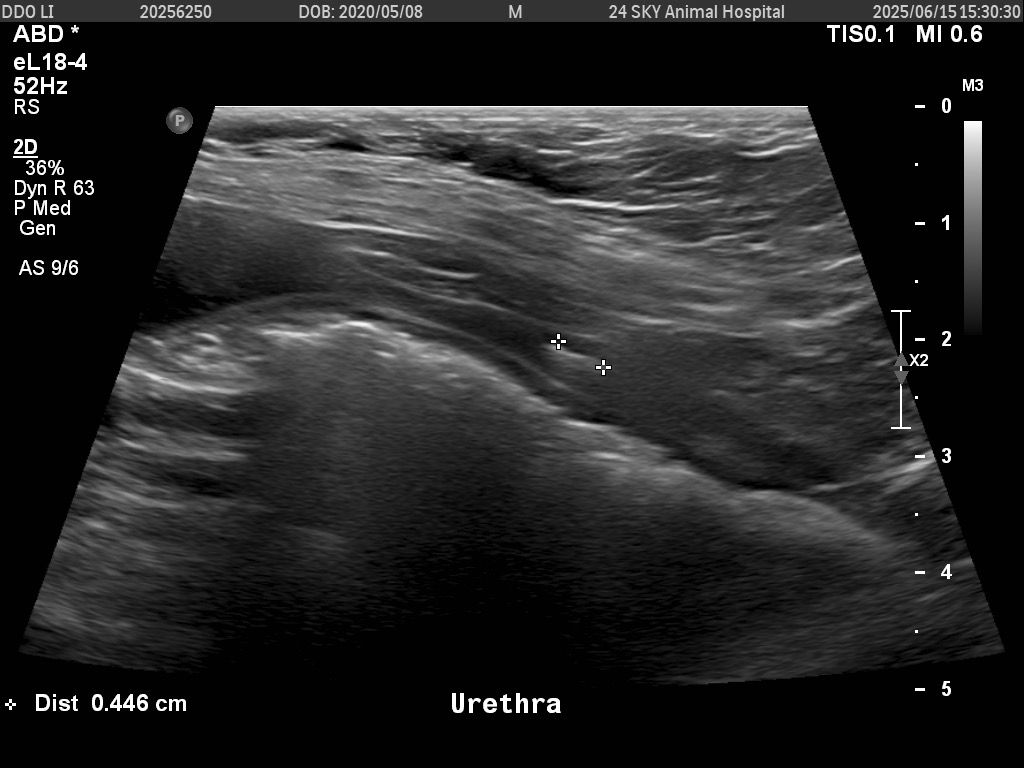

그런데 오늘 6월 15일 다시 내원했을 때

요도 쪽에 0.446cm 결석 1개,